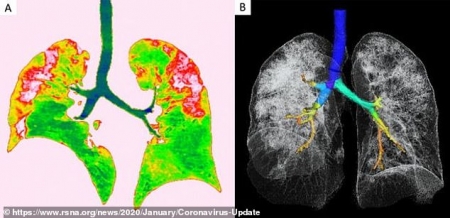

আপনাদের বোঝার সুবিধার্থে আক্রান্ত রোগীর বুক ও সাধারণ রোগীর বুকের দুইটি এক্সরের ছবি নিচে দেওয়া হলোঃ

করোনা আক্রান্ত রোগীর ফুসফুস বা LUNGS।

শাহ আজিজ বলেছেন: সি টি স্ক্যানে আরও পরিচ্ছন্ন ছবি পাওয়া যায় । মার্চ মাসে উহানের রোগীদের স্ক্যান চিত্র হংকঙের একটি পত্রিকা ছাপত । পড়ে পুরো লকডাউন আর ইন্টারনেট বন্ধ হয়ে গেলে আমরা খবর পাওয়া থেকে বঞ্চিত হই । একটি ক্লোজ ছবিতে দেখাচ্ছিল গুরুতর সংক্রমিত এবং বেচে যাওয়া এক রোগীর লাংস । গ্লাস গলে গেলে যেমন দুমড়ে মুচড়ে যায় সেই রোগীর তাই হয়েছে । হংকঙ্গের ডাক্তার বলছিলেন এই ধরনের বেচে যাওয়া রোগী বাকি জীবন লাংসের বিবিধ ওষুধ খেয়ে বেচে থাকবেন । আমি খুজব সেই ক্লিপ সেভ করেছিলাম কিনা । এক্সরে নয় সিটি স্ক্যান বেশি উপযোগী , খরচ বেশি বলে তা করা হয় না ।

রোকনুজ্জামান খান বলেছেন: আপনার কথার গ্রহনযোগ্যতা আছে এবং আমি আপনার সাথে একমত। সিটি স্ক্যান অফ চেষ্ট করালে আরো সুন্দর ও পরিচ্ছন্ন ভাবে আমরা দেখতে পারি। তবে আমাদের দেশের ডাক্তাররা কভিড পরীক্ষার কাছেই দায়বদ্ধ। এখনো অনেক জেলা শহর গুলোতে সিটি স্ক্যান অফ ব্রেন ছাড়া অন্য কোন সিটি করানো হয় না। এক্সরে আমাদের জন্য সহজলভ্য ও অল্পমূল্যের তাই এটিকে প্রাধান্য দেওয়া হয়েছে। আপনার কার্যকরী মন্তব্যের জন্য সাধুবাদ ও অন্তরিক ধন্যবাদ জানাচ্ছি। এবং সুস্বাস্থ্যে কাটান প্রতিটি সময়, আপানি এবং আপনার পরিবার সেই কামনা রইলো।

Covid-19 stage 10-13days।